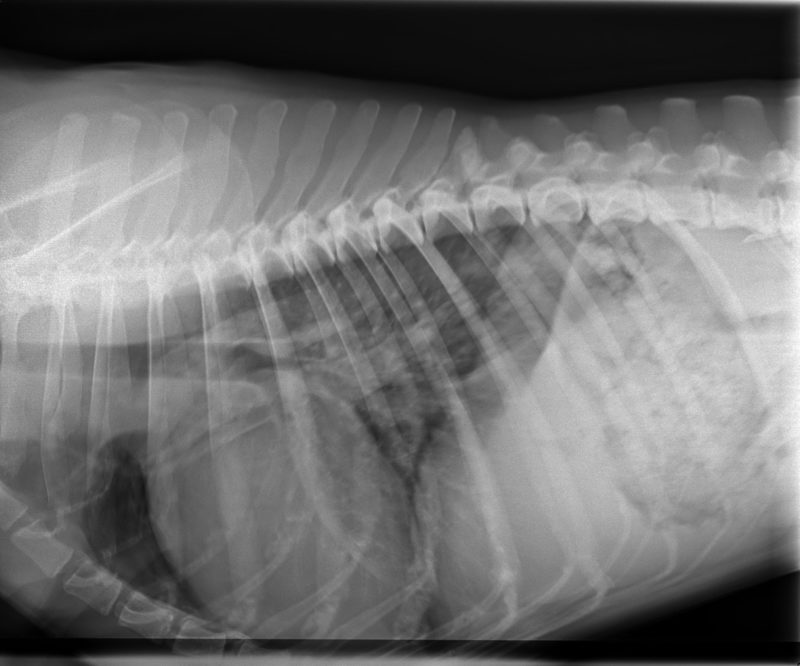

Außerdem habe ich eine Röntgenaufnahme von Momos Brustkorb angefertigt. Diese zeigte dann auch eine Verschattung der hinteren Lungenlappen. Die Herzsilhouette war vergrößert und es war eine Stauung der Lungenvenen zu erkennen, was auf ein kardial bedingtes Lungenödem schließen lässt. Es befand sich also Wasser in Momos Lunge.